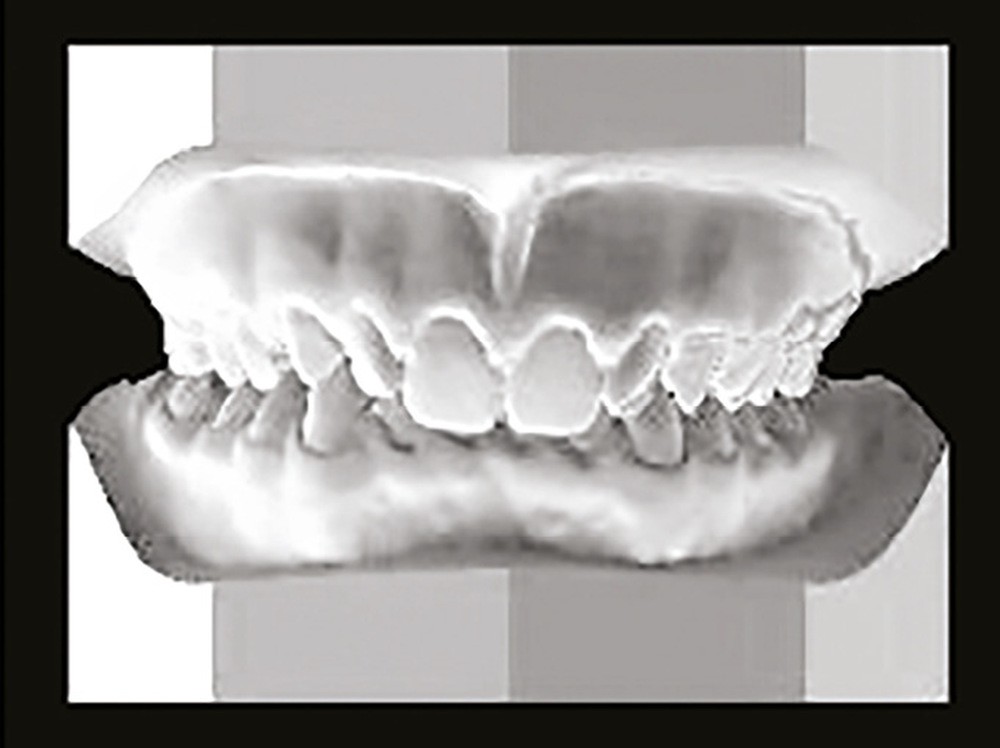

Son profil convexe s’inscrit dans un contexte de classe II squelettique par rétrognathie mandibulaire normodivergente sur un schéma de Classe II/2 avec supraclusion et encombrement modéré (fig. 1 à 7).

La formule dentaire est complète, avec un léger retard d’évolution des deuxièmes molaires (fig. 8).